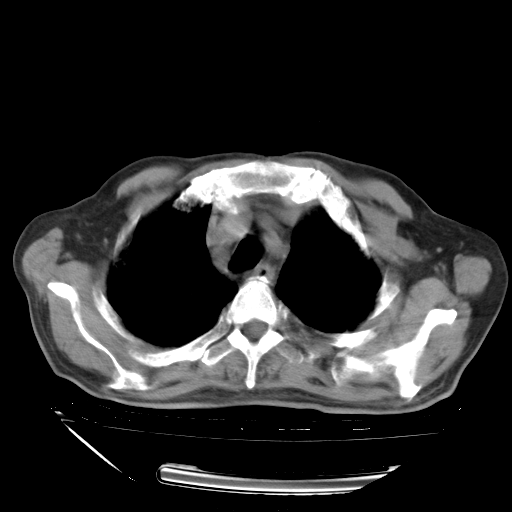

甲强龙80mg/日+抗结核治疗(异烟肼+利福霉素+乙胺丁醇)10天。复查肺部CT。

94186 2 1 .bmp

94186 3 1 .bmp

94186 3 2 .bmp

94186 3 3 .bmp

94186 3 4 .bmp

94186 3 5 .bmp

94186 3 6 .bmp

94186 3 7 .bmp

94186 3 8 .bmp

94186 3 9 .bmp